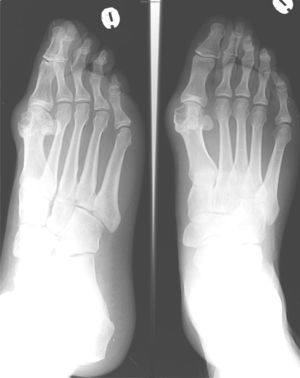

En la analítica se objetivó una uricemia de 9,4mg/dl y GGT 166 U/dl. El resto de los parámetros (hemograma, TSH, CPK, Factor reumatoide, HLA B27, anticuerpos antipéptido cíclico citrulinado, inmunoglobulinas, orina y uricosuria de 24h) fueron normales. Se realizó radiografía de pie izquierdo (fig. 1) que mostró erosiones marginales de bordes bien delimitados en la cabeza del primer metatarsiano, con aumento de partes blandas adyacente. La radiografía de rodilla izquierda (fig. 2) presentaba lesiones líticas de bordes bien delimitados en epífisis tibial y cambios degenerativos incipientes a nivel femorotibial. Se realizó artrocentesis de la rodilla izquierda. Con visualización de cristales de urato monosódico en el líquido sinovial (LS). El cultivo del LS fue negativo.